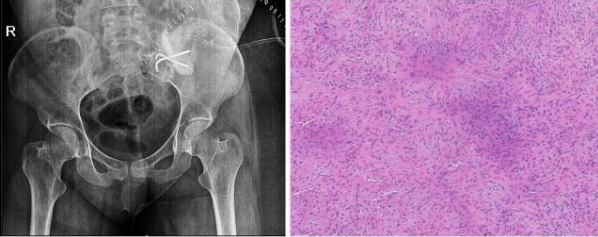

Case 4- 21 year old female patient who presented with pain and swelling of the left lower back area since 8 months. Upon clinic radiological evaluation – on x ray was found to have a lytic lesion in the left postero-superior iliac wing and MRI showed T2 intermediate to hyper-intense lesion on the left iliac wing with cortical breech and extra-osseous soft tissue component involving the iliacus muscle anteriorly and gluteus medius posteriorly measuring 5.9x5.6x6.3 cm with T2 hypointense rim around the lesion Fig-10. Histopathology proved to be fibromatosis and after multidisciplinary team meeting patient was planned for extended curettage and reconstruction Fig-11. Reconstruction was done using poly-methyl methacrylate cement and two K-wire for stabilisation with post-op Histopathology confirming the diagnosis Fig-12. Upon one year of follow up patient does not have any complaints and doing well.